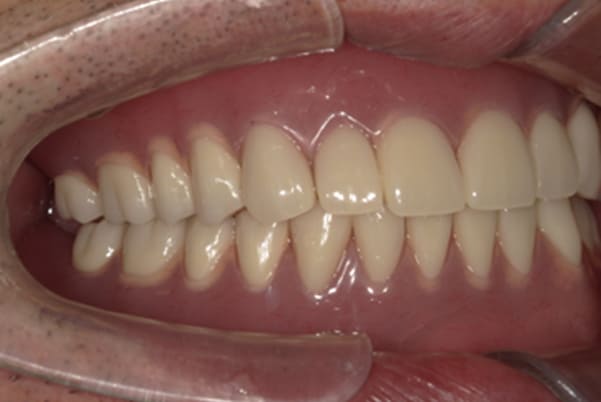

こちらは、口を少し開いた時の治療前と治療後の

口元です。

正面から見た時にクラスプが目立たないように、

歯ぐきになじむ素材にて入れ歯を製作し、痛くなく自然に馴染み快適に生活を送れるようになりました。